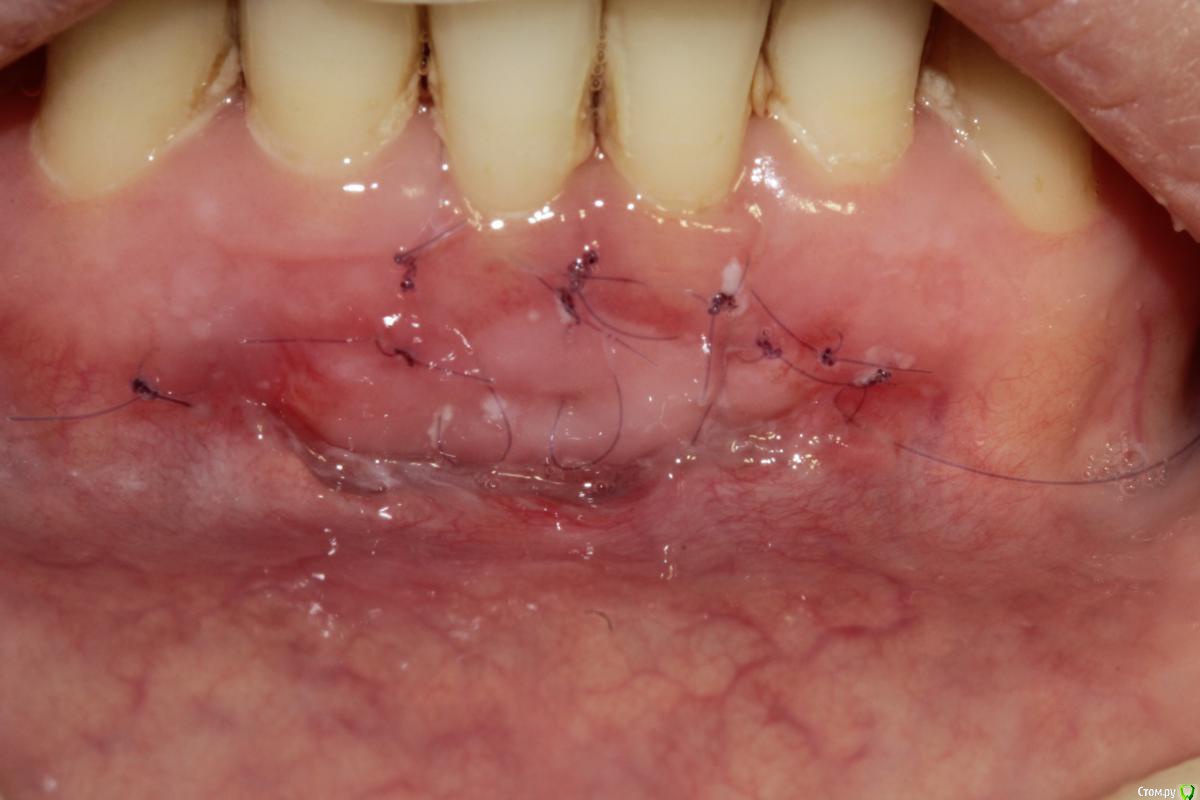

Чертков Александр Опубликовано 11 февраля, 2015 Поделиться Опубликовано 11 февраля, 2015 (изменено) увеличение ЗПКД, профилактика рецессии, при улыбке не видноЕсть более "эстетичные" и менее инвазивные способы. Рецессии?...Где? Я бы такой уровень уздечки даже и не подумал как-то изменять. А если уж очень хочется, то можно было выполнить довольно простую френотомию(эктомию). Минусы я полагаю Вы и сами видите. [/quote Вы имеете ввиду отличие по цвету?Нет, цвет - дело второстепенное, а вот два грубых рубца получили...тем самым, действительно, поспособствовали возможности рецессии. Изменено 11 февраля, 2015 пользователем Чертков Александр Ссылка на комментарий

АнтонТЛТ Опубликовано 11 февраля, 2015 Поделиться Опубликовано 11 февраля, 2015 Надо было просто биотип утолщить 1 Ссылка на комментарий

Dr.Aubov Опубликовано 11 февраля, 2015 Поделиться Опубликовано 11 февраля, 2015 Теперь рецессия будет Ссылка на комментарий

Dc.Petrov Опубликовано 12 февраля, 2015 Автор Поделиться Опубликовано 12 февраля, 2015 Никаких показаний к хирургии нет Не согласен, мб на фото не видно, но СДС у 31,41 не более 1-2 мм от края маргинальной десны.При инфильтрации анестетика это особенно очевидно. Условия для рецессий есть. Надо было просто биотип утолщить Согласен вот два грубых рубца получили...тем самым, действительно, поспособствовали возможности рецессии ? Не совсем понял Ваше утверждение. Буду наблюдать в отдаленные сроки. Если Вам интересно продолжу тему с фото через 3, 6, 12 месВсех благодарю за комментарии Ссылка на комментарий